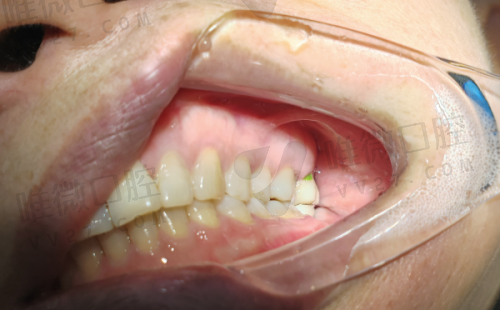

种植牙、根管治疗、牙齿修整、活动义齿、牙齿洁治

维齿美口腔在罗定地区以实惠价格、高还原度修复方案见长,是本地许多“老牙友”的选择之一。尤其适合想做经济实用型修复或口腔基础治疗的人群。该院注重患者复诊跟进,医生沟通细致,特别善于处理高龄患者的牙槽骨吸收问题,适合中老年人看牙。